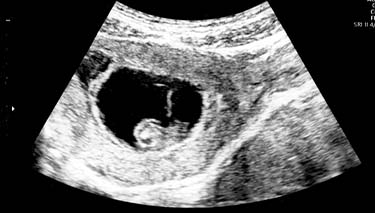

It's common for women to have a 7 week ultrasound and for many, it's their first real look at their baby. A dating scan at 7 weeks helps to confirm baby's presence and development, but it can also help to rule out pregnancy complications.

Your embryo will be measured from the top of its head, the crown to its bottom or rump . This is called the crown-rump-length or CRL. This is because it is the longest portion of the baby's body gives an ideal measurement of its growth and development.

An average length of the embryo at 7 weeks is between 5-9 mm long. The average weight is less than 1 gram. Obviously, every pregnancy is unique and individual factors influence the size of the embryo.

In very early pregnancy, the embryo and pregnancy sac may simply be too small to see very much at all. It's the shape and general structures which are more obvious. And if present, a tiny heart beat. The average number of beats per minute (BPM) is between 100-180 between 6-7 weeks of gestation.

At seven weeks of gestation it is still too early to identify what gender (sex) the baby will be. It is also impossible to do a thorough foetal screening assessment because it is still just too premature in terms of embryonic development. However, general mass structures such as a head and body can generally be seen in the embryo at seven weeks.